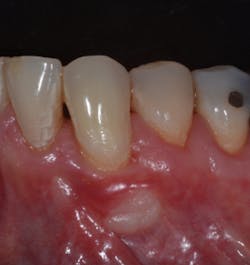

Figure 4b

TheBernotti V-Y Flapis a minimally invasive coronally advanced flap consisting of a pedicle flap with a V incision made apically to the recession defect. This technique protects the interdental tissue, does not expose the underlying bone, and provides a better blood supply, resulting in less crestal bone loss. As you can see in the video, this noninvasive soft-tissue grafting technique allows for coronal movement of the marginal tissue with no tension from the suture on the vertical slope in creating the "Y" part of the flap (figures 5 and 5a). It also allows for excellent soft-tissue match (figure 6) and is an alternative to conventional grafting techniques.